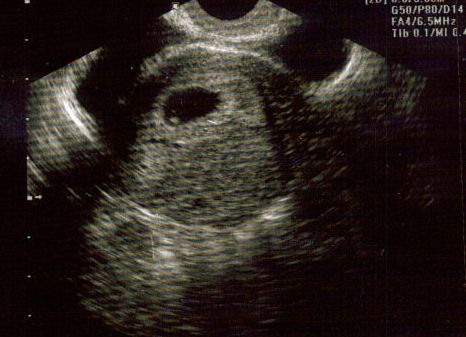

@ 6 Weeks